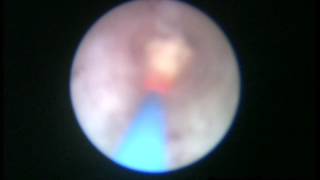

TURis Plasma Vaporization εξάχνωση προστάτη Δρ. Κυμηνάς Laser λιθοθρυψία με εύκαμπτο ουρηρτηροσκόπιο Εξελκυσμός λίθου ουρητήρα Διουρηθρική όγκου ουροδόχου κύστεως 1 www.kyminas-urology.gr Διουρηθρική προστατεκτομή TURis Δρ. Κυμηνάς Ευάγγελος www.kyminas-urology.gr TUR-P Διουρηθρική προστατεκτομή TURis 1 Δρ. Κυμηνάς Ευάγγελος www.kyminas-urology.gr Laser λιθοθρυψία λίθου ουρητήρα Δρ. Κυμηνάς Ευάγγελος www.kyminas-urology.gr ουρητηροσκόπηση καρκίνος ουρητήρα Δρ. Κυμηνάς Ευάγγελος www.kyminas-urology.gr Ουρητηροκήλη Δρ. Κυμηνάς Ευάγγελος www.kyminas-urology.gr Διουρηθρική θηλώματος κύστεως υψηλού βαθμού κακοήθειας Kyminas-urology.gr